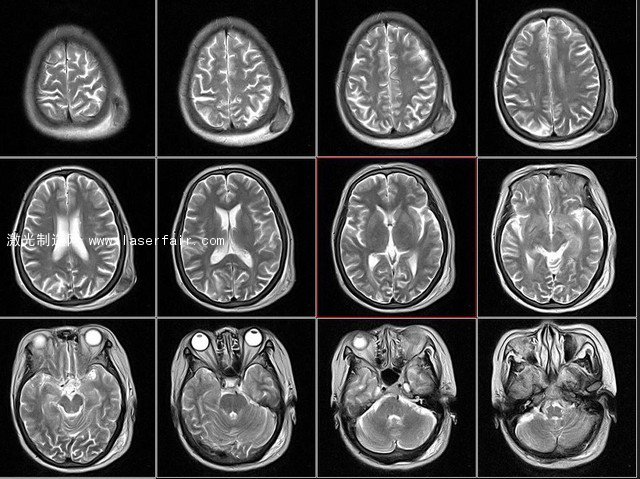

人腦核磁共振切面圖 圖源ququliao.com

富蘭克林學(xué)院的科學(xué)家借助核磁共振技術(shù)掃描出一位40歲男子的2D腦部切片,再用計(jì)算機(jī)組合成為腦白質(zhì)的3D模型。然而到這里出現(xiàn)了一個(gè)難題:人腦3D數(shù)據(jù)太過龐大和復(fù)雜,即使查看或者分享已經(jīng)很困難,更不用提3D打印出來了。人們總是在說,3D打印技術(shù)擅長制造復(fù)雜的形狀,這次卻被復(fù)雜形狀所打敗。